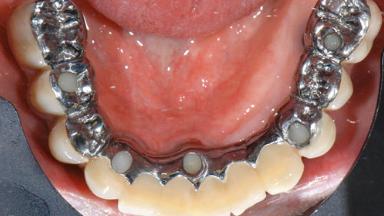

A 77-year-old male patient was referred for the management of frequent and repeated acrylic fracture of his existing mandibular fixed full-arch implant-supported metal/acrylic prosthesis. He also complained about softtissue soreness and the lack of retention and stability of his maxillary removable partial metal/acrylic prosthesis. Both prostheses had been delivered two years previously as part of his full-mouth rehabilitation (caries, tooth wear, tooth fracture). His medical history revealed high blood pressure, controlled with the use of antihypertensive medication.

# of Implants 5

Prosthesis Type FDP

Retention Screw-retained, with 4 or more splinted implants Screw-retained, with 4 or more splinted implants